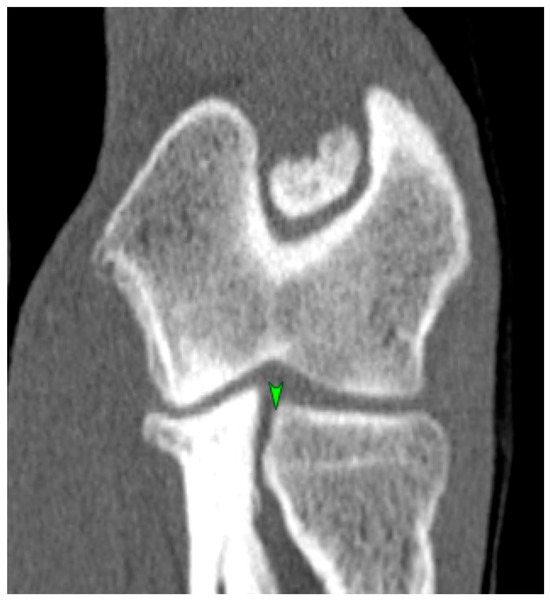

2.5. Measurement Techniques

3.1.2. CT Results of the Elbow Joints

3.2.2. CT Results for the Elbow Joints